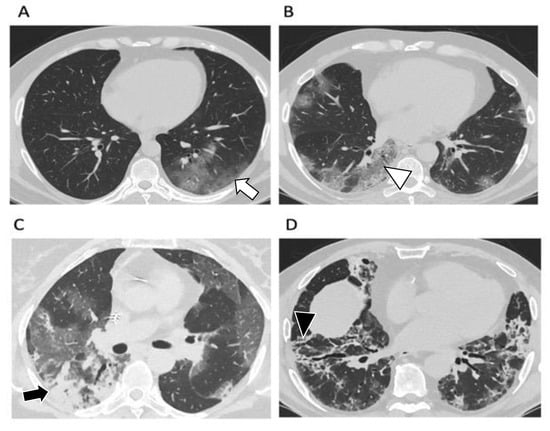

2.2. Typical CT Findings

2.3. CT Findings Evolution

2.5. Complications